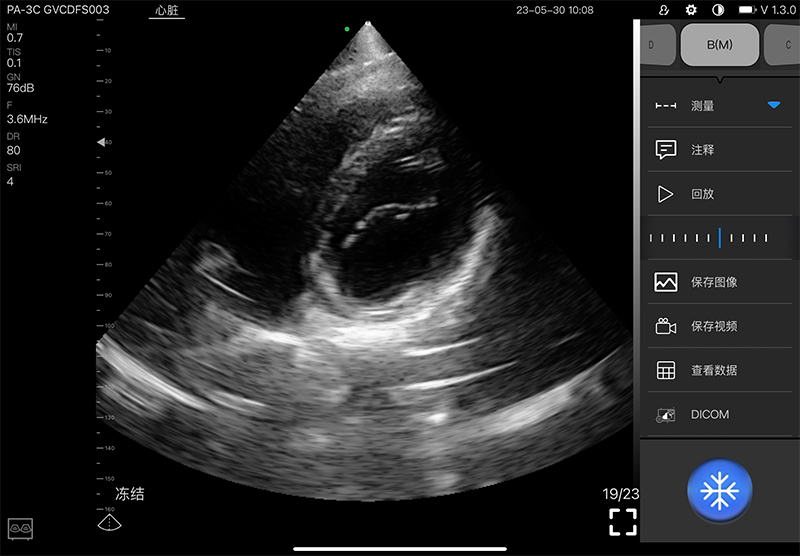

5PA

5PA Plus

- Scanning mode: Electronic phased array

- Display mode: B, B/M, and Color, PW, CW, PDI

- Frequency: central 2.8MHz, cardiac reverse harmonic

3.6mhz, and the transcranial fundamental 2.2MHz

- Display Angle: 80°